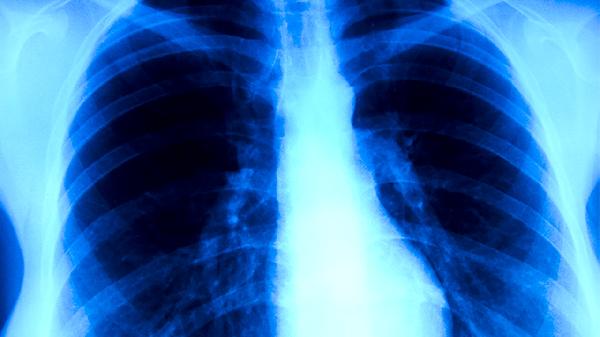

肺結(jié)核的常見(jiàn)表現(xiàn)癥狀主要有咳嗽咳痰、咯血、胸痛、發(fā)熱盜汗、體重下降等。肺結(jié)核是由結(jié)核分枝桿菌感染引起的慢性傳染病,主要通過(guò)呼吸道傳播,可累及肺部及其他器官。

咳嗽咳痰是肺結(jié)核最常見(jiàn)的癥狀,早期多為干咳或少量白色黏液痰。隨著病情進(jìn)展,痰量可能增多,部分患者可出現(xiàn)黃綠色膿性痰??人猿掷m(xù)時(shí)間較長(zhǎng),通常超過(guò)2周,且常規(guī)抗感染治療無(wú)效。肺結(jié)核患者的痰中可能含有結(jié)核分枝桿菌,具有傳染性。若出現(xiàn)長(zhǎng)期咳嗽咳痰不愈,建議及時(shí)就醫(yī)進(jìn)行痰涂片檢查或胸部影像學(xué)檢查。